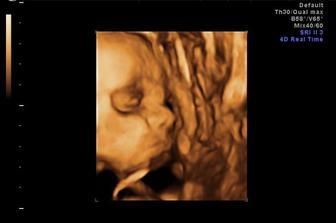

Po troch neúspešných pokusoch to prišlo nečakane ale o to viac sa tešiiiiiiiiime....Toto tehu prebiehalo bez vačšiich komplikacii až na pár strašnych momentov ked nám vyšli pozitívne testy na toxoplazmozu ale len na pol hodinku lebo potom nám to lekár zrušil že som to prekonala ako dieťa takže nič sa nedeje...v 13tt sme si boli trochu oddychnut v nemocnici na 5 dni pre špinenie ale všetko chvalabohu dobre dopadlo a teraz už každu chvíľu čakáme na nášho maličkého anjelika...

Narodil som sa na 39tt cisarskym rezom v utorok 9.9.2009 O 8:50 s mierami 2840g a 47 cm...